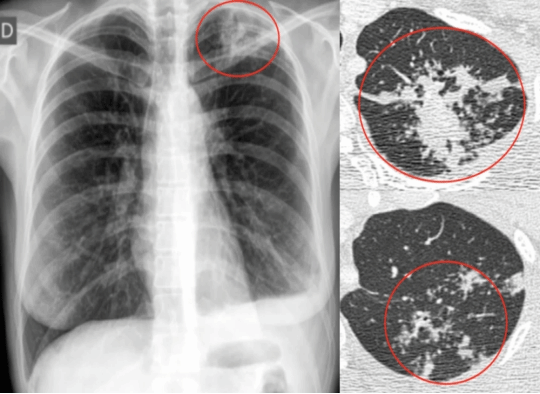

1、放射诊断---DR和CT

在肺结核的诊断中扮演着重要角色,特别是影像学检查如DR和CT检查,是肺结核诊断的关键工具。它们可以帮助医生,发现早期轻微的病变,评估病变的严重程度。放射诊断不仅用于肺结核的诊断,还用于治疗过程中的监测。通过定期的影像学检查,医生可以评估治疗效果,调整治疗方案。

(DR和CT上的结核灶)